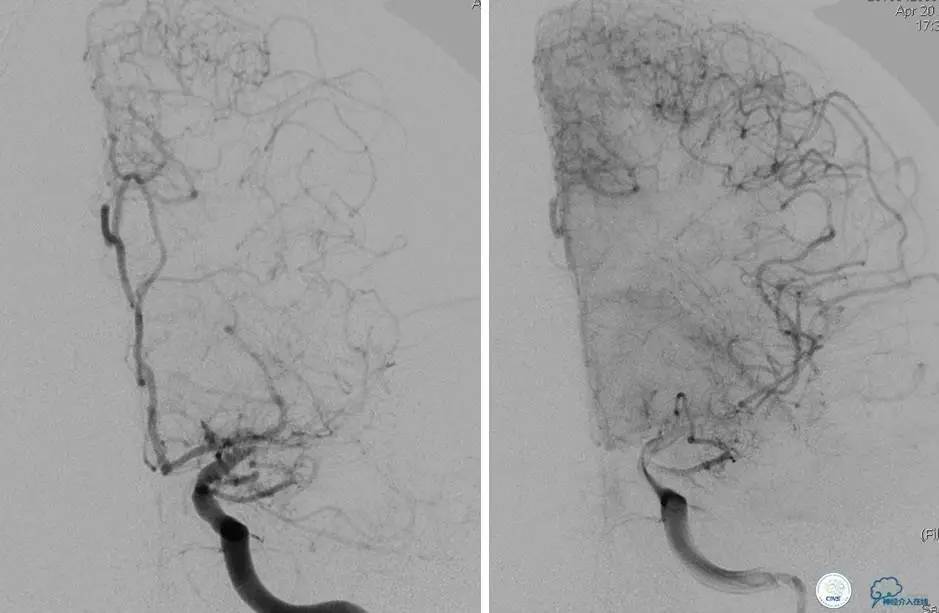

患者:49岁男性,左侧偏瘫1个月,药物治疗、康复训练效果不好,转我院,肌力0~1级。

core-clilnical明显不匹配,是介入开通的合适患者。

造影评价血管、判断闭塞段,微导丝谨慎穿过闭塞段,微导管造影,交换技术,球囊扩张,Enterprise支架。在后扩张时导丝刺破M3段血管,蛛网膜下腔出血(SAH)。

微导管进入破裂血管,栓塞弹簧圈1枚,出血停止,结束手术。继续双抗,术后2天肌力2级,神经功能恢复明显加快。

术后即刻和6天后CT,患者无明显临床症状。

半年后复查造影,无支架内再狭窄,可见弹簧圈,患者恢复至自己柱杖行走。